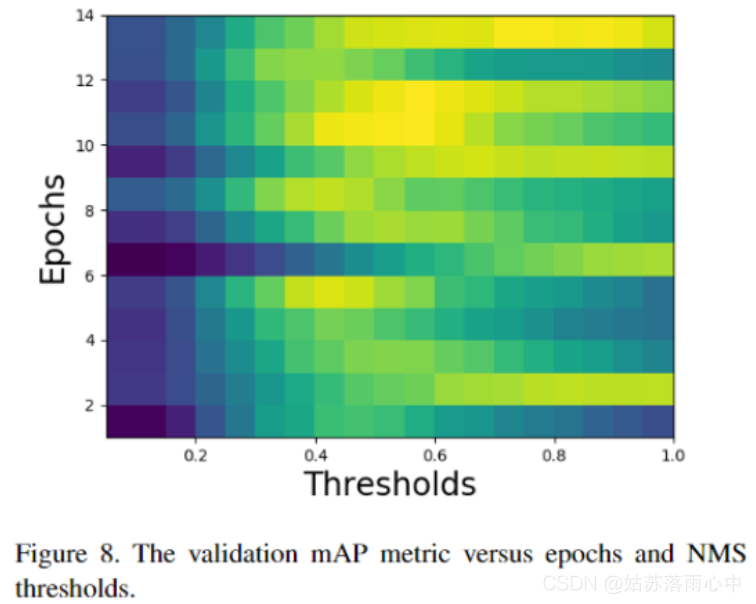

由于标记过程不同,训练和测试集的最大抑制(NMS)算法也有所不同。NMS阈值对mAP指标值产生了巨大影响。图8显示了针对不同训练时期和NMS阈值的验证mAP指标变化。验证集的最佳NMS阈值在各个时期之间存在显着差异,取决于模型,其最佳范围在0.45和1之间。

检测模型的结果可能在各个epoch之间发生显着变化,并且很大程度上取决于阈值。在应用NMS算法和优化阈值之前,将相同模型的4折交叉验证的输出合并。